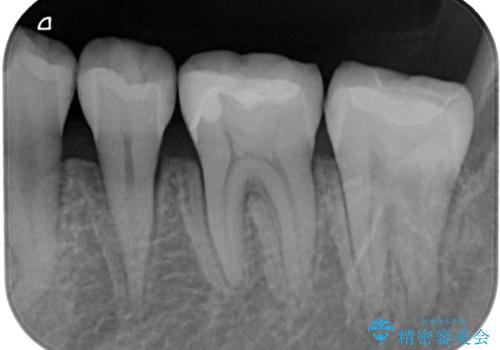

特に異常もなく見た目、噛み合わせともに満足していただけました。

ラバーダム防湿を行い、セラミックの接着をすることで、唾液や血液などの接着阻害因子を排除することができます。

歯と歯の間の虫歯をコンポジットレジンや保険のメタルインレーで治すと段差ができたりして清掃性が悪くなるので、セラミックインレー修復やゴールドインレー修復などの適合の良い詰め物で治療することをオススメします。